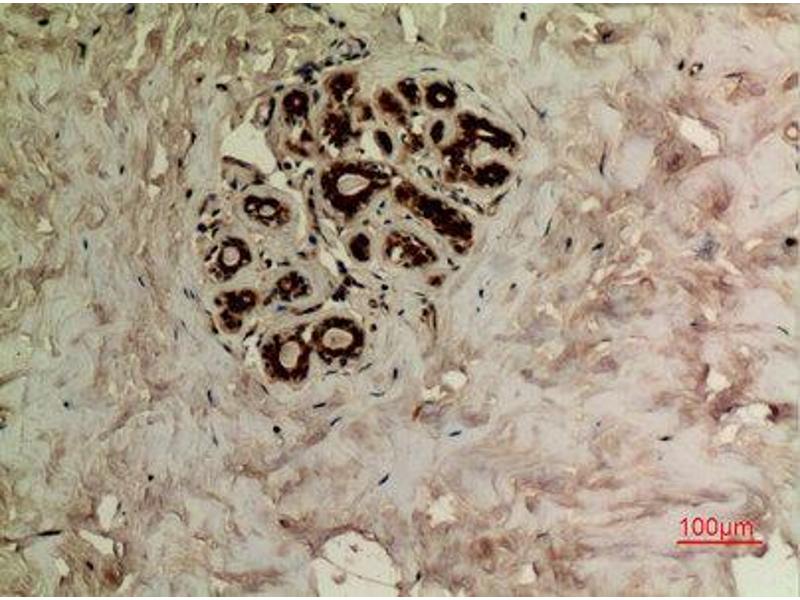

Immunohistochemistry (IHC) refers to the process of detecting antigens in cells of a tissue section by exploiting the principle of antibodies binding specifically to antigens in biological tissues. Its widely used in the diagnosis of abnormal cells such as those found in cancerous tumors and in basic research to understand the distribution and localization of biomarkers and differentially expressed proteins in different parts of a biological tissue. Visualising an antibody-antigen interaction can be accomplished in a number of ways. In the most common instance, an antibody is conjugated to an enzyme, such as peroxidase, that can catalyse a colour-producing reaction or tagged to a fluorophore.